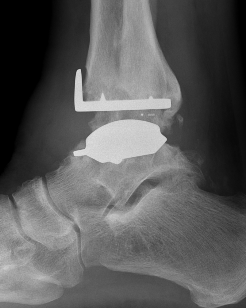

Talar dome resurfacing

- jig to make chamfer cuts

Insert mobile / fixed bearing